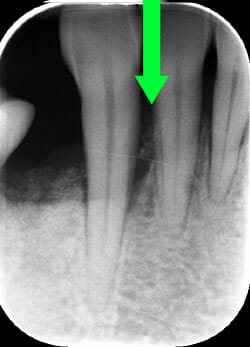

Endorale prima e dopo la cura della parodontite

Con terapia parodontale fotodinamica non chirurgica: si noti la ricrescita naturale dell’osso e del tessuto parodontale.